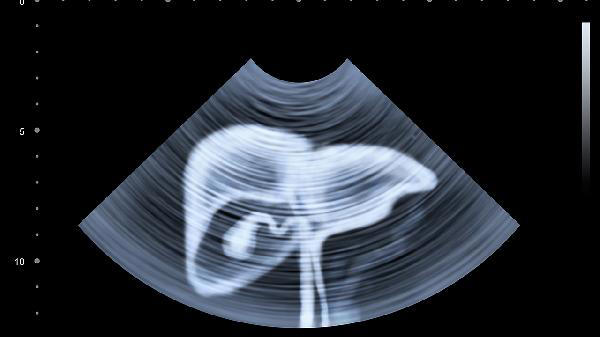

重要提醒:这些症状可能单独出现,也可能多个同时发生。特别是慢性肝病患者,哪怕只出现其中一个表现,也要尽快做肝功能、超声等检查。春季是养肝黄金期,也是肝病容易加重的季节。现在放下手机摸摸自己的右肋下,如果有闷胀感,建议抽空做个肝脏体检。记住,肝病的早期干预和治疗效果天差地别!